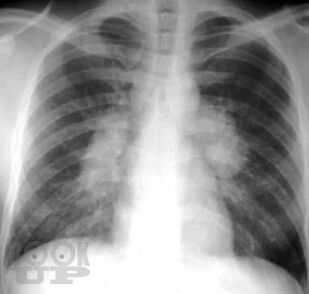

Учебное пособие предназначено для ординаторов, обучающихся по специальности 31.08.49 Терапия и слушателей дополнительного профессионального образования. В настоящем учебном пособии изложены современные представления по распространенности, этиологии, патогенезу, клинике, диагностике, дифференциальной диагностике и лечению саркоидоза органов дыхания, кожных покровов, почек, кардиального и костно-мышечного саркоидоза. Имеются тестовые задания и ситуационные задачи для самоконтроля знаний, издание иллюстрировано рисунками, схемами и таблицами.